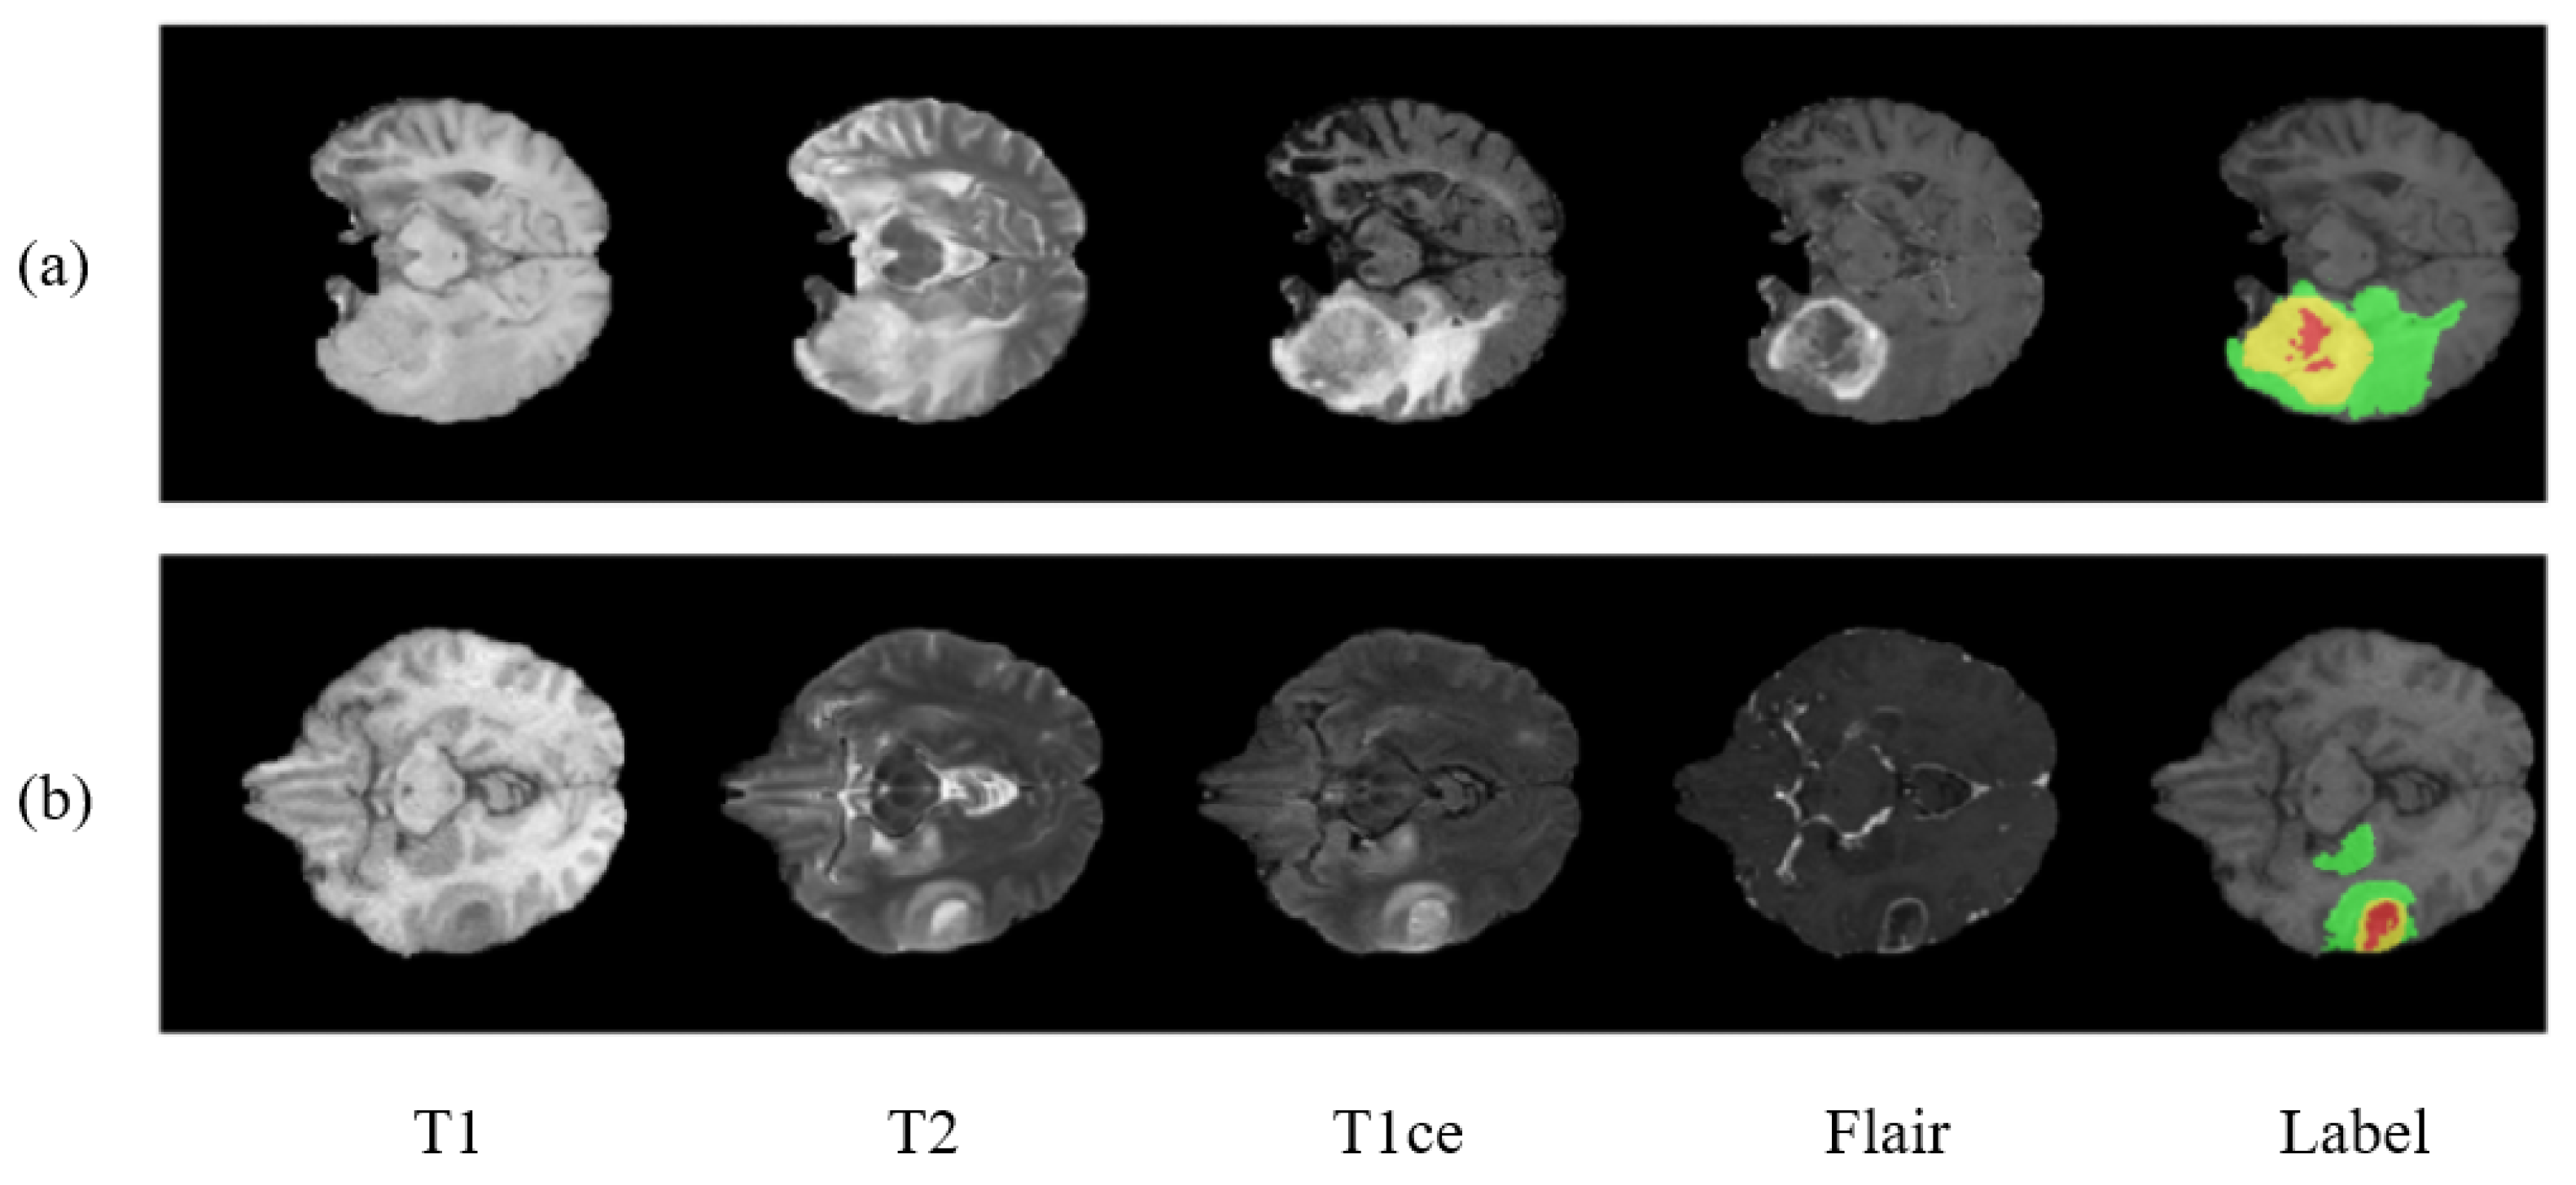

2. Datasets

- Enhancing tumor.

- Necrosis and non-enhancing tumor.

- Edema.

- Healthy tissue.